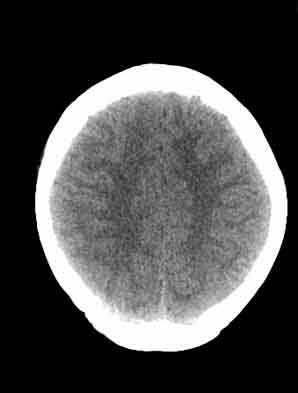

脑沟裂消失,脑白质密度似有减低,考虑脑炎。

大脑表面脑沟裂消失,颅压高的表现,经常遇到这样的现象,都没有一个明确的结论,望高人指点。

脑沟裂消失,脑白质密度似有减低,考虑脑炎。期待结果验证。